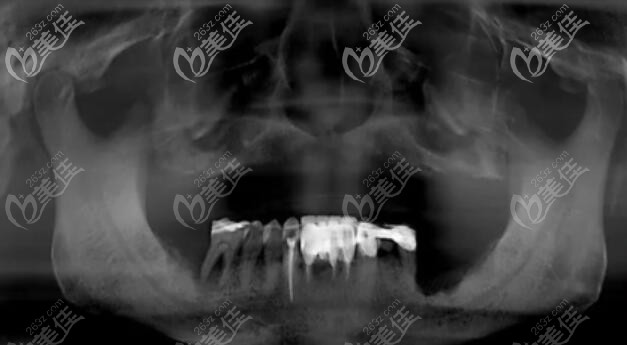

取下活動(dòng)義齒后口腔狀況↓↓↓

上半口做種植牙后的CT照片↓↓↓